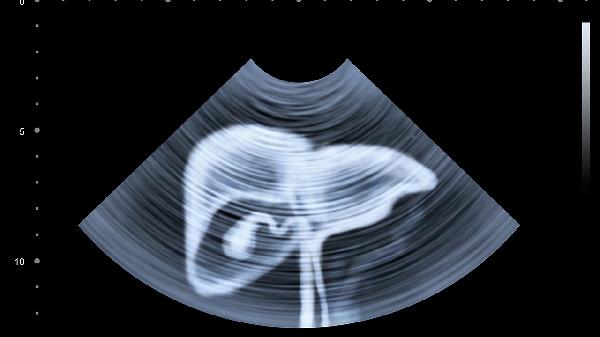

腹部外伤后腹胀多由腹腔内出血或肠内容物外漏引起。腹腔积血达到500毫升以上即可出现明显腹胀,肠管破裂后气体进入腹腔也会导致腹胀。患者常自觉腹部膨隆、紧绷感,可能伴随肠鸣音减弱或消失。严重腹胀可能影响呼吸运动,出现呼吸困难症状。